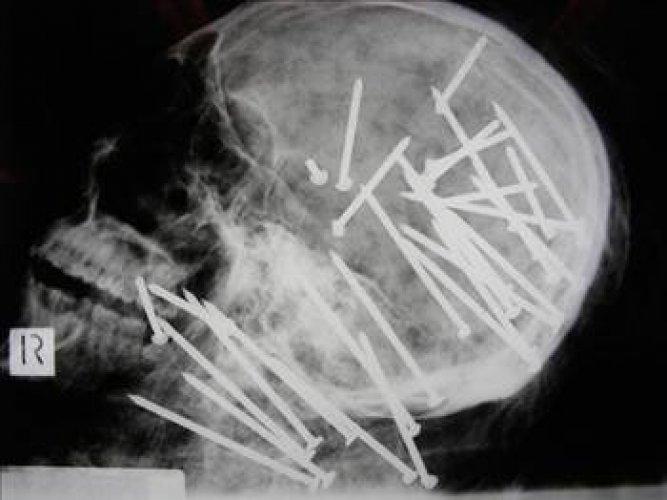

En ilginç tıbbi vakalar 4/39

27 yaşındaki Chen'in cesedini inceleyen uzmanlar, büyük şok yaşadı. Chen'in kafatasının röntgeni çekildiğinde kafasına bir sürü çivi çakılmış olduğu görüldü. İncelemeden sonra Chen'in çivi tabancası ile öldürüldüğü anlaşıldı.